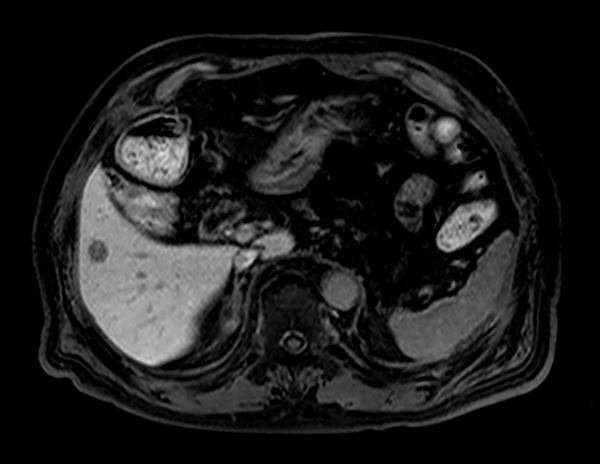

Axial T1w in/out phase